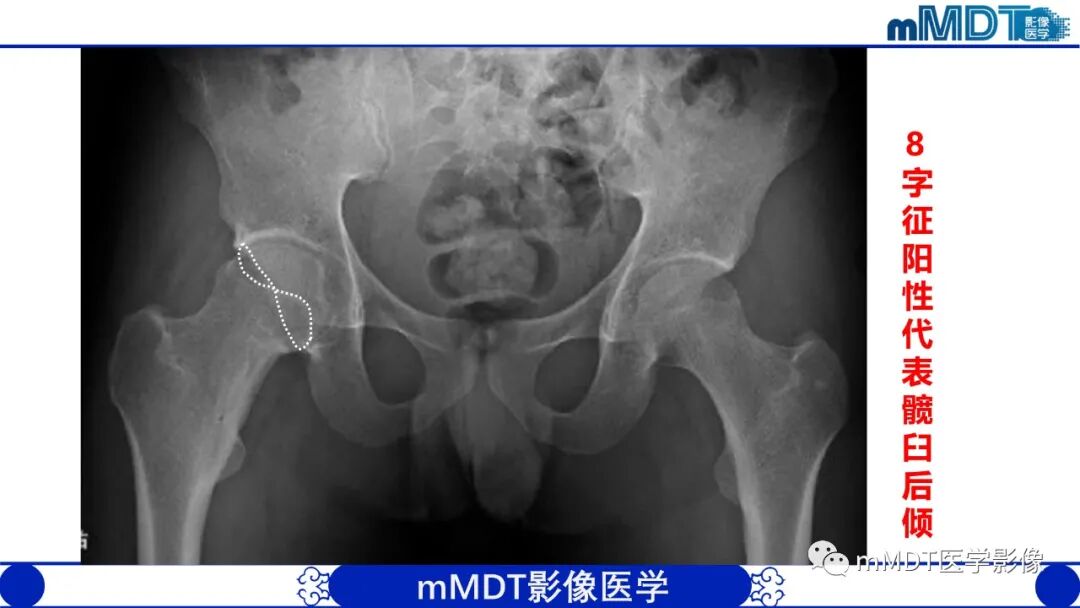

1.X线平片对本病的诊断是重要的,还应作相关测量,包括髋臼角、CE角、髋臼覆盖率(股骨头裸露程度)等。成人以测量CE角较为准确,而且简便。

2.在骨盆前后位片上髋臼顶短小,CE角小于30度,伴或不伴有髋臼倾斜度过大(髋臼角大于45度),股骨头裸露25%以上,可诊断为髋臼发育不良。需要注意的是,有时髋臼边缘继发骨性增生,使髋臼外缘代偿性加宽(假臼缘形成),可表现为CE角减小不明显甚至不变小;而股骨头肥大、变形、外移或半脱位时则可出现由于股骨头中心外移造成的CE角过度变小和股骨头裸露增大,在这种情况下,观察髋臼角的增大及髋臼深度的改变有重要意义。